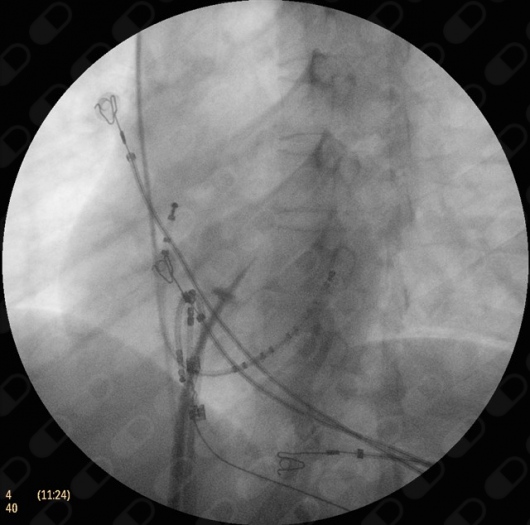

Cateterismo cardíaco, estudio de taquicárdias

Las taquicardias son los ritmos anormalmente rápidos del corazón, esta pueden tener múltiples causas, pero el diagnóstico preciso es muy importante ya que muchas de ellas pueden ser curables por medio de estudios de cateterismo que es la introducción a través de la venas de las ingles de cables capaces de realizar un electrocardiograma por dentro del corazón y así determinar el sitio exacto de la arritmia. Esta es la tarea del electrofisiólogo, siendo unos de los campos de mayor impacto en beneficio de los pacientes.

Estudio electrofisiológico terapéutico (ablación vías accesorias)

Este es uns intervención que se realiza desde las venas de la ingles, en ocasiones desde las del cuello u hombro, donde se llega al corazón con la ayuda de cables. Estos con capaces de detectar el sitio exacto de donde provienen las arritmias, como las vías accesorias o el el síndrome de Wolff Parkinson White, lo que permite que con la ayuda de otro cable con una pequeña punta de metal lleguemos a ese sitio y lo cautericemos, con lo que lograríamos una alta tasa de curación al quitar para siempre la vía accesoria o el Wolff Parkinson White, esto lo realiza sólo el electrofisiólogo.

Estudio electrofisiológico terapéutico (taquicardias ventriculares)

Esta es una intervención que se realiza desde las venas de la ingles, en ocasiones desde las del cuello u hombro, donde se llega al corazón con la ayuda de cables. Estos con capaces de detectar el sitio exacto de donde provienen las arritmias, lo que permite que con la ayuda de otro cable con una pequeña punta de metal lleguemos a ese sitio y lo cautericemos, con lo que lograríamos la curación de la arritmia. En el caso de las taquicardias ventriculares, es elemental contar con este tipo de intervención ya que han demostrado la alta efectividad de curación en unos casos, o de control de los episodios en otros y así mejorando la calidad de vida. Esto lo realiza sólo el electrofisiólogo.